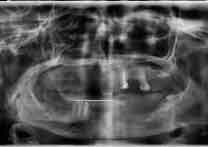

(22)

Before Treatment

OPG (Pre Treatment)

After Areatment

OPG (Post Treatment)

Case of full mouth rehabilitation All teeth extracted Upper single complete denture and lower Implant supported denture